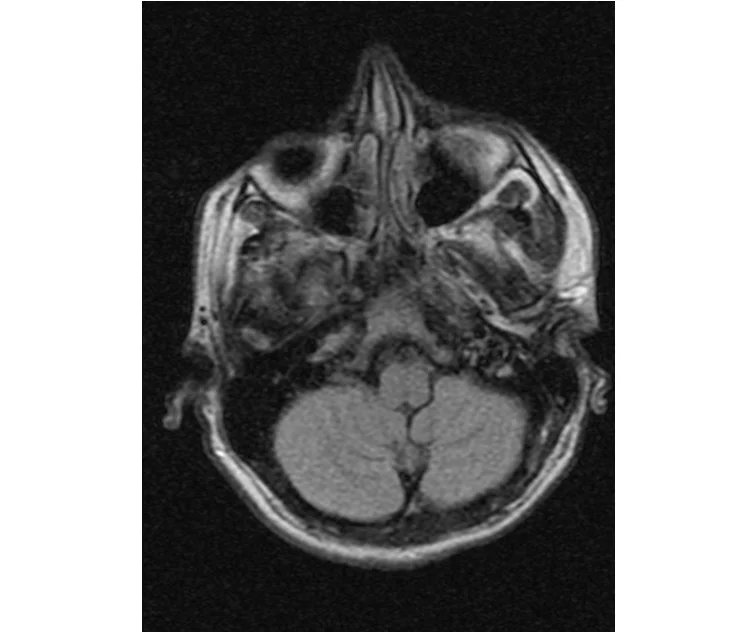

глянте на снимки томографии плиз

делал в обласной на siemense.В заключении выданом мне через 15мин.после мрт (легкая дегидрация)

Меня смутил факт выдачи заключения через 10мин(наверно они у них зарание напечатаные)я не медик.достаточно мимолётного взгляда на снимки?А вы видете на них гидроцефалию? Я лиш спросил куда идти с результатами томографии?и не хотел никого роздражать.

Я попросил взглянуть на снимки и сказать видна.ли на них гидроцефалия?или куда обратится за консультацией по этому вопросу?В мрт снимках наверно розбирается любой нервопатолог(я так предположил)

Я уже говорил, что независимо от того, есть на МРТ гидроцефалия или нет, лечиться тебе нужно только в том случае, если есть какие-либо проявления болезни, иначе на все эти анализы можешь забить... Но давай все-таки разберемся с томограммой.

Ты разместл здесь несколько миниатюр и хочешь, чтобы врач по ним создал полноценное объемное изображение в натуральную величину, а потом осмотрел его со всех сторон и дал заключение? Но ведь это невозможно. Это просто насмешка над врачом, это издевательство над здравым смыслом. Принеси Букеру уменьшенный в 50 раз снимок зуба и спроси у него, в каком состоянии там корневые каналы. Или давай я дам тебе скрин со спутниковой карты города и попрошу тебя описать, какого цвета и какой модели запечатленная со спутника машина, какой у нее гос.номер, сколько в ней пассажиров, сколько из них мужчин и сколько женщин...